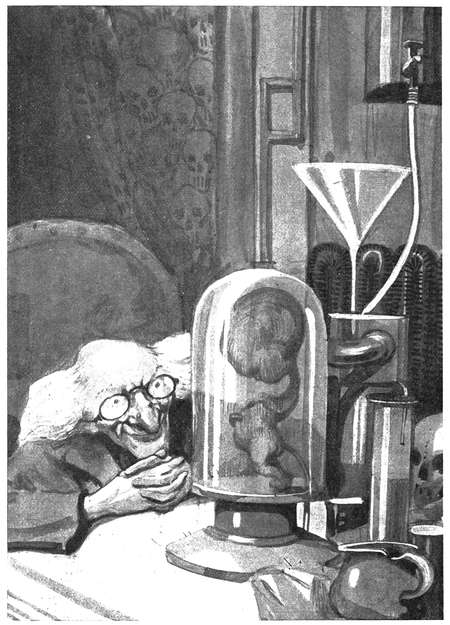

Mit anderen Worten: wir bedürfen der Entdeckung eines elektrochemischen Prozesses, durch welchen die Krankheitskeime im Gewebe, in der Lymphe und im Blute getötet werden, ohne den Zellen des lebendigen Körpers Schaden zu tun. Und daß dieses Problem wirklich gelöst werde, gehört zu den aussichtsreichsten Verheißungen der allernächsten Zukunft. Dann wird jedes Opfer jeder wie immer gearteten Krankheit in einem einzigen Tage wieder hergestellt werden können, und jede Krankheit wird mit einem Schlage verschwinden. Der aber, der dieses Problem endgültig lösen wird, wird der größte Wohltäter des Menschengeschlechts werden, größer als die Weltgeschichte jemals einen gehabt hat oder je wieder haben wird. Für einen anderen neben ihm ist kein zweiter Platz mehr vorhanden.

Chemiker, Elektriker und Physiker sollten dieser Aufgabe die ernsteste Beachtung schenken und tun es wohl auch, und ich möchte ihnen da gleich folgenden Wink geben, der ihnen möglicherweise von Nutzen sein könnte:

Seit geraumer Zeit ist es bekannt, daß, wenn man ein Diaphragma in einen Elektrolyten bringt und einen elektrischen Strom von ausreichenden Volts hindurchschickt, der Inhalt der einen Elektrodenkammer solange durch das Diaphragma hindurch in die andere eingepreßt wird, bis sich ein gewisser Druckunterschied zwischen den Lösungen der beiden Kammern eingestellt hat. Diesen Vorgang nennt man Elektro-Osmose oder Kataphorese. Gerber verwenden Elektro-Osmose beim Gerben von Häuten, indem sie eine Gerblösung auf das Fell einwirken lassen; sie sparen auf diese Weise viel Zeit und viel Geld.

Meine Anregung geht nun dahin, den ganzen menschlichen Körper als einen Teil des Diaphragmas in der Elektro-Osmose oder Kataphorese zu verwenden und so heilkräftige bezw. Krankheitskeime zerstörende Chemikalien in und durch das Hautgewebe, die Lymphe und das Blut zu pressen. Könnte nicht zum Beispiel, wenn der menschliche Körper einen Teil einer solchen Scheidewand darstellen müßte, eine Chlorlösung in die eine der Kammern gegossen und ein derartig starker elektrischer Strom hindurch geschickt werden, daß das Chlor in und durch das menschliche Zellengewebe, die Lymphe und das Blut gepreßt würde, wodurch alle Krankheitskeime zerstört werden müßten, ohne daß dadurch die Gewebe und die flüssigen Stoffe des Körpers auch nur im geringsten in Mitleidenschaft gezogen würden?

Chlor ist nämlich eines der stärksten und wundervollsten Desinfektionsmittel, das unsere Wissenschaft kennt; von ihm genügt eine weit schwächere Lösung als von den meisten anderen, unsere Krankheitskeime zerstörenden Chemikalien, wie zum Beispiel Karbolsäure (Phenol), Aetzsublimat und übermangansaures Kali. Wenn die Bandagen einer frischen Wunde sofort mit einer schwachen Chlorlösung, die ein wenig mit gewöhnlichem Kochsalz gemengt ist, angefeuchtet und feucht gehalten werden, so vernarbt die Wunde fast immer ohne jede Eiterung und hinterläßt keinerlei Schmerzhaftigkeit an der betreffenden Stelle. Das ist doch ein augenscheinlicher Beweis dafür, daß eine ausreichend starke Chlorlösung angewendet werden darf, um infizierende Krankheitskeime zu töten, ohne die Zellengewebe des menschlichen Körpers in Mitleidenschaft zu ziehen.

Der menschliche Organismus ist gleichsam eine komplizierte Maschine. Er ist eine Art elektrischer Generator. Sein Blut ist alkalisch, während die Lymphe oder der Körpersaft seines Fleisches sauer ist; beide sind durch eine undurchdringliche Membran von einander getrennt, so daß ein Mensch wohl an einer Erkrankung des Blutes leiden kann, ohne dabei kranke Lymphgefäße haben zu müssen. Umgekehrt können wieder seine Lymphgefäße erkrankt sein, wie dies beispielsweise bei der Tuberkulose der Lymphgefäße, die wir unter den Namen Skrofulose kennen, der Fall ist, ohne daß er an Tuberkulose des Blutes erkrankt zu sein braucht. Um daher jeden Krankheitskeim in der Lymphe und im Blut, in den Knochen und in den Muskeln sicher zu zerstören, wäre es notwendig, den ganzen Körper einheitlich mit einem Desinfektionsmittel zu durchdringen.

Und das zu erreichen, das muß das Ziel der desinfizierenden Elektro-Osmose sein. Ein Ziel, dem wir — ich wiederhole es — heute schon nahe sind.